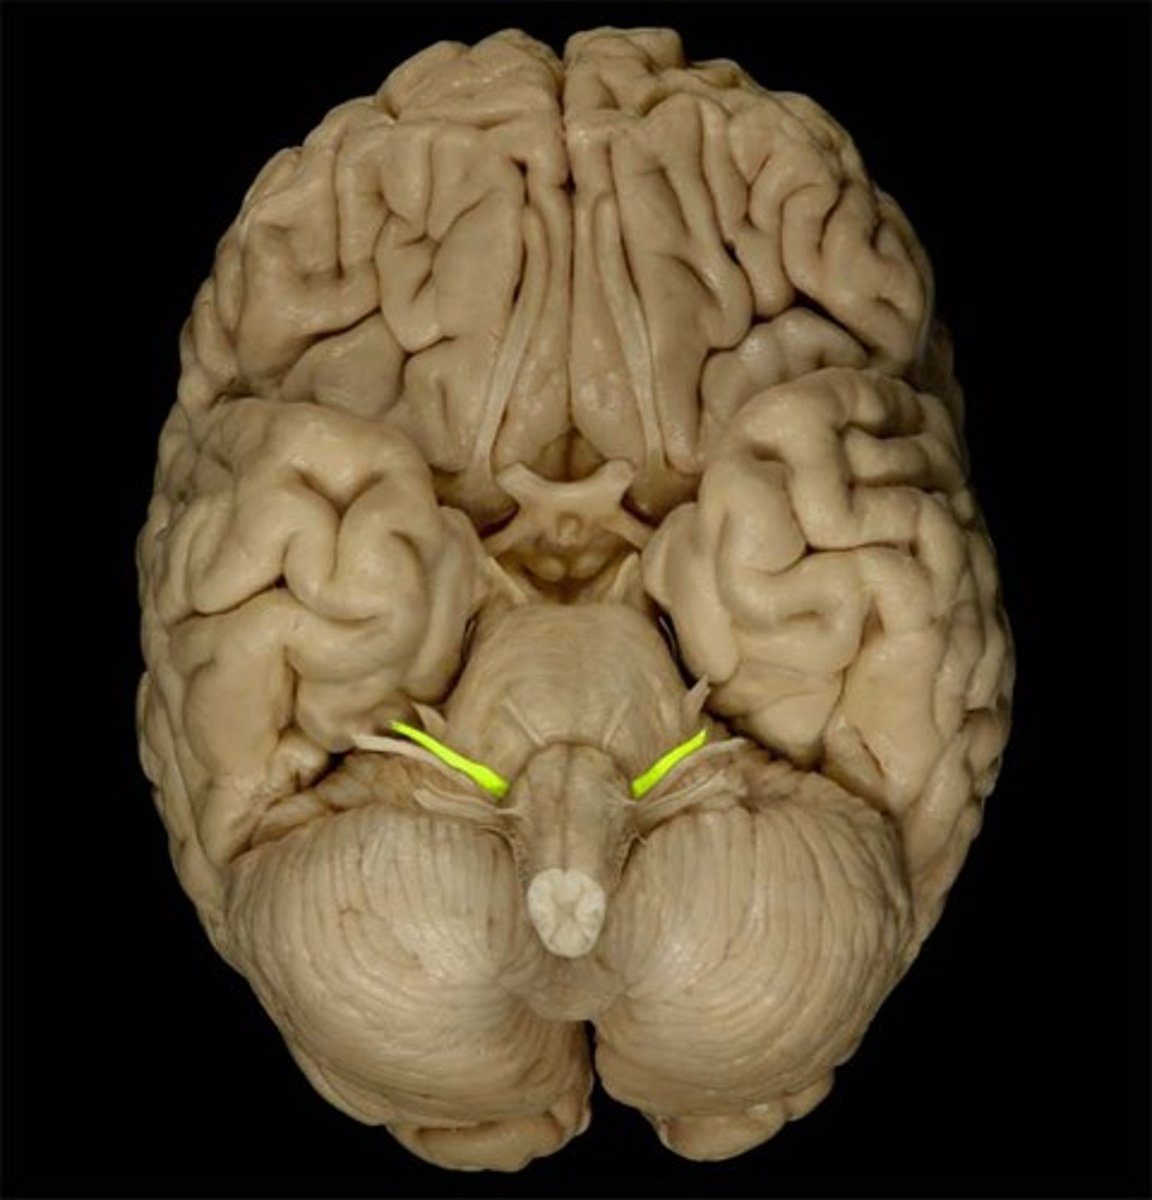

optic nerve (CN II)

Sensory cranial nerve related to vision

optic chiasm

point at which optic nerve fibers cross in the brain

optic tracts

the continuation of the optic nerve fibers beyond the optic chiasma

primary visual cortex

•Located within occipital lobe; receives, processes, stores visual information